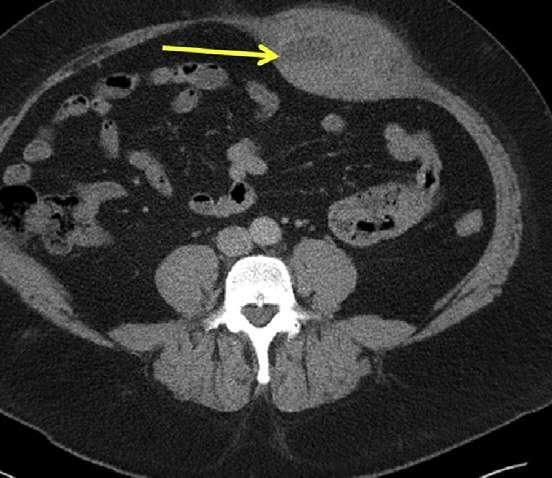

2.便秘性结肠炎:

老年、长期卧床者慢性长期便秘导致肠腔内粪块嵌塞,压迫肠壁造成肠炎,在直肠、乙状结肠中多见, 严重者可造成肠壁坏死和穿孔。CT表现典型:1.巨大粪块;2.肠壁增厚; 3.肠壁周围渗出,粪便经肠壁局部缺损膨出、肠周出现气泡提示肠穿孔可能。